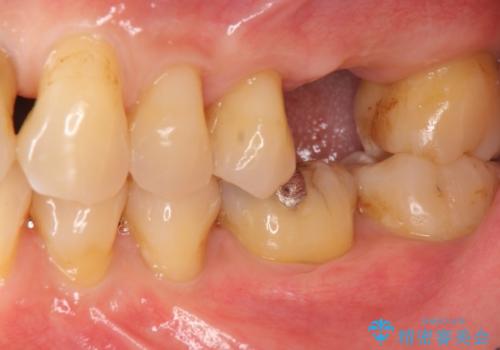

奥歯の欠損 インプラントによる咬合機能回復

- 奥歯を失い噛めないことの治療を希望され来院されました。

臨在する歯が虫歯もなく健全であるため、ブリッジではなくインプラントを用いた機能回復を計画します。

- 50万円(ストローマンインプラント・骨造成・チタンカスタムアバットメント・ジルコニアクラウン)費用は治療当時の料金となります

インプラントを用いることで、隣の歯を削ることなくしっかりと噛む機能を回復させることができます。